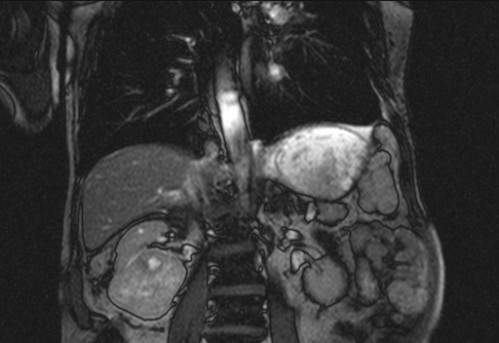

Auffälliges Abdomen bei der Vorsorgeuntersuchung einer älteren Dame

ICD: C64

68 Jahre alte Frau. Sie geht zur Darmspiegelung im Rahmen ihrer Krebsvorsorgeuntersuchung. Der Internist bemerkt bei der ergänzenden sonografischen Untersuchung des Abdomens einen auffälligen Befund.